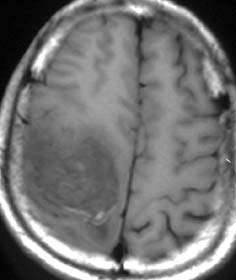

▼原来,明琴并不只是一般「瘦弱和爱哭闹的宝宝」,她其实患有重度的身心障碍,而且还有脑水肿、癫痫、过动和斜视等健康问题,这突如其来的噩耗让把明琴当成心肝宝贝般疼爱、照顾的何女士崩溃了。